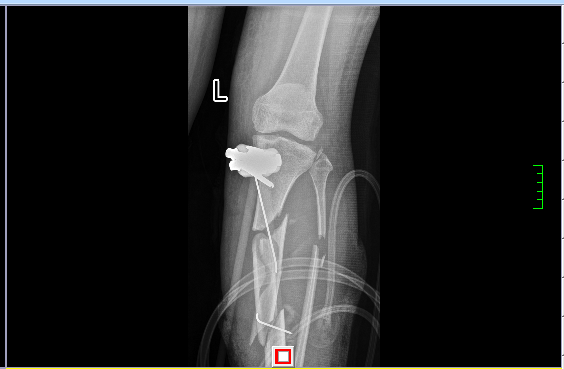

术前患者左侧胫腓骨粉碎性骨折

骨搬运术后2年去除外固定装置左胫骨骨缺损(约18cm)两端成功合拢,生长良好